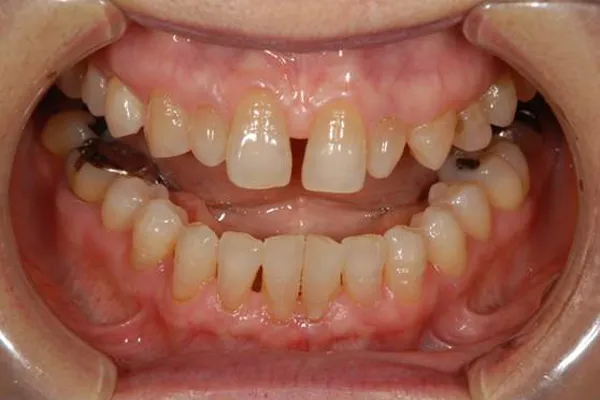

初診

歯石除去で来院されました。

除去後、話を聞くと上顎の前歯の歯と歯の間が離れていることが

以前より気になっていると仰られ、治療計画を立案。

レントゲン写真を撮影。

口腔内写真の撮影

残っている歯の問題点などを解析